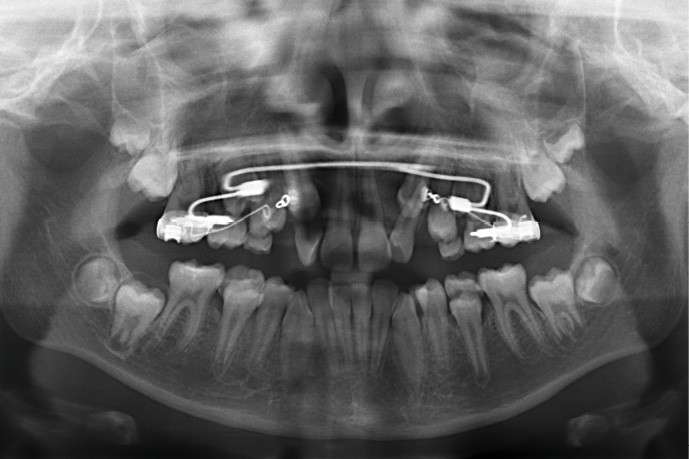

Sur la radiographie panoramique, on observe une transposition des canines maxillaires en place d’incisives latérales, au contact des racines de 11 et 21.

Des bagues molaires sont essayées et adaptées sur 16 et 26 et un arc transpalatin à mémoire de forme (Nitanium Palatal Expander -Ortho Organizers, USA) dont la dimension est sélectionnée à partir de la mesure de la distance inter-molaire mandibulaire est ligaturé à celles-ci hors bouche. L’ensemble est scellé avec un ciment verre-ionomère après refroidissement au spray à -45 °C de la partie en NiTi pour insertion facilitée.

Sept jours après la pose du dispositif, une intervention chirurgicale est réalisée sous anesthésie locale lors de laquelle a lieu le collage de dispositifs de traction sur 13 et 23. Les canines temporaires sont extraites dans le même temps opératoire.

À ce stade, une radiographie panoramique est réalisée pour s’assurer de l’intégrité des racines, contrôler les axes dentaires et planifier le repositionnement de certaines attaches ainsi que le collage des tubes sur les secondes molaires en cours d’éruption.